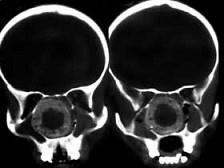

问题 女,14岁,渐进性鼻塞2年余,右眼肿痛数月,CT如图所示,应诊断为 ( )

选项 A、筛骨结核 B、筛骨骨化性纤维瘤 C、筛骨骨纤维瘤 D、筛骨软骨瘤 E、筛骨骨肉瘤

答案 B